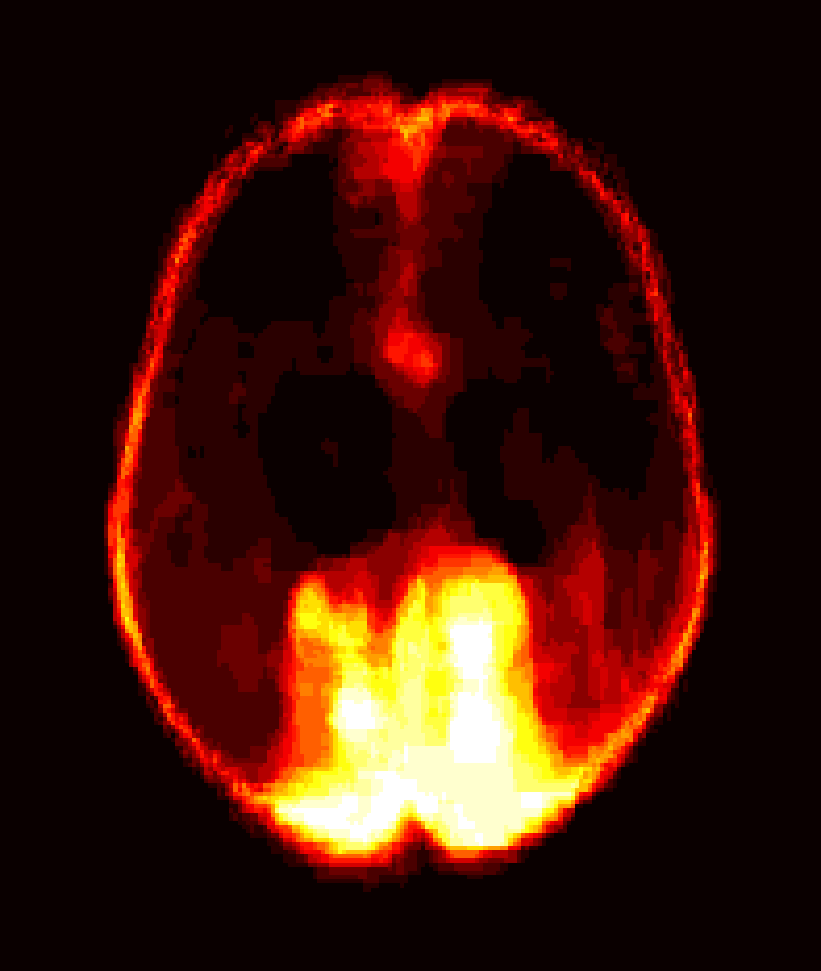

[Uncaptioned image] [Uncaptioned image] [Uncaptioned image] [Uncaptioned image]

(a) (b) (c) (d)

Figure 8: Example BRATS image with its decomposition result in atlas space. (a) Input image after pre-processing; (b) quasi-normal image L+M𝐿𝑀L+M; (c) non-brain image S𝑆S; (d) pathology image T𝑇T.

In addition to extracting the brain from pathological datasets, our method also allows for the estimation of a corresponding quasi-normal image in atlas space, although this is not the main goal of this paper. Fig.8 shows an example of the reconstructed quasi-normal image (L𝐿L) for an image of the BRATS dataset, as well as an estimation of the pathology (pathology image T𝑇T and non-brain image S𝑆S). Compared to the original image, the pathology shown in the quasi-normal image has been greatly reduced. Hence this image can be used for the registration with a normal image or a normal atlas. This has been shown to improve registration accuracy for the registration of pathological images [27]. Furthermore, an estimate of the pathology (here a tumor) is also obtained which may be useful for further analysis. Note that in this example image the total variation term captures more than just the tumor. This may be due to inconsistencies in the image appearance between the normal images (obtained from OASIS data) and the test dataset. As our goal is atlas alignment rather than quasi-normal image reconstruction or pathology segmentation, such a decomposition is acceptable, although we could improve this by tuning the parameters or applying regularization steps as in [27].